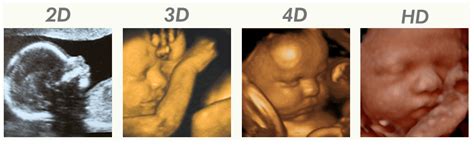

Echo op eigen wens zonder medische indicatie (Pretecho)

Een pretecho is een echo op niet-medische indicatie. Dit is een echo om u een extra kijkje in de buik te geven. Er vindt geen medische beoordeling van de baby plaats. U kunt hierbij denken aan een geslachtsbepalende-, 2D-, 3D- of 4D-echo.